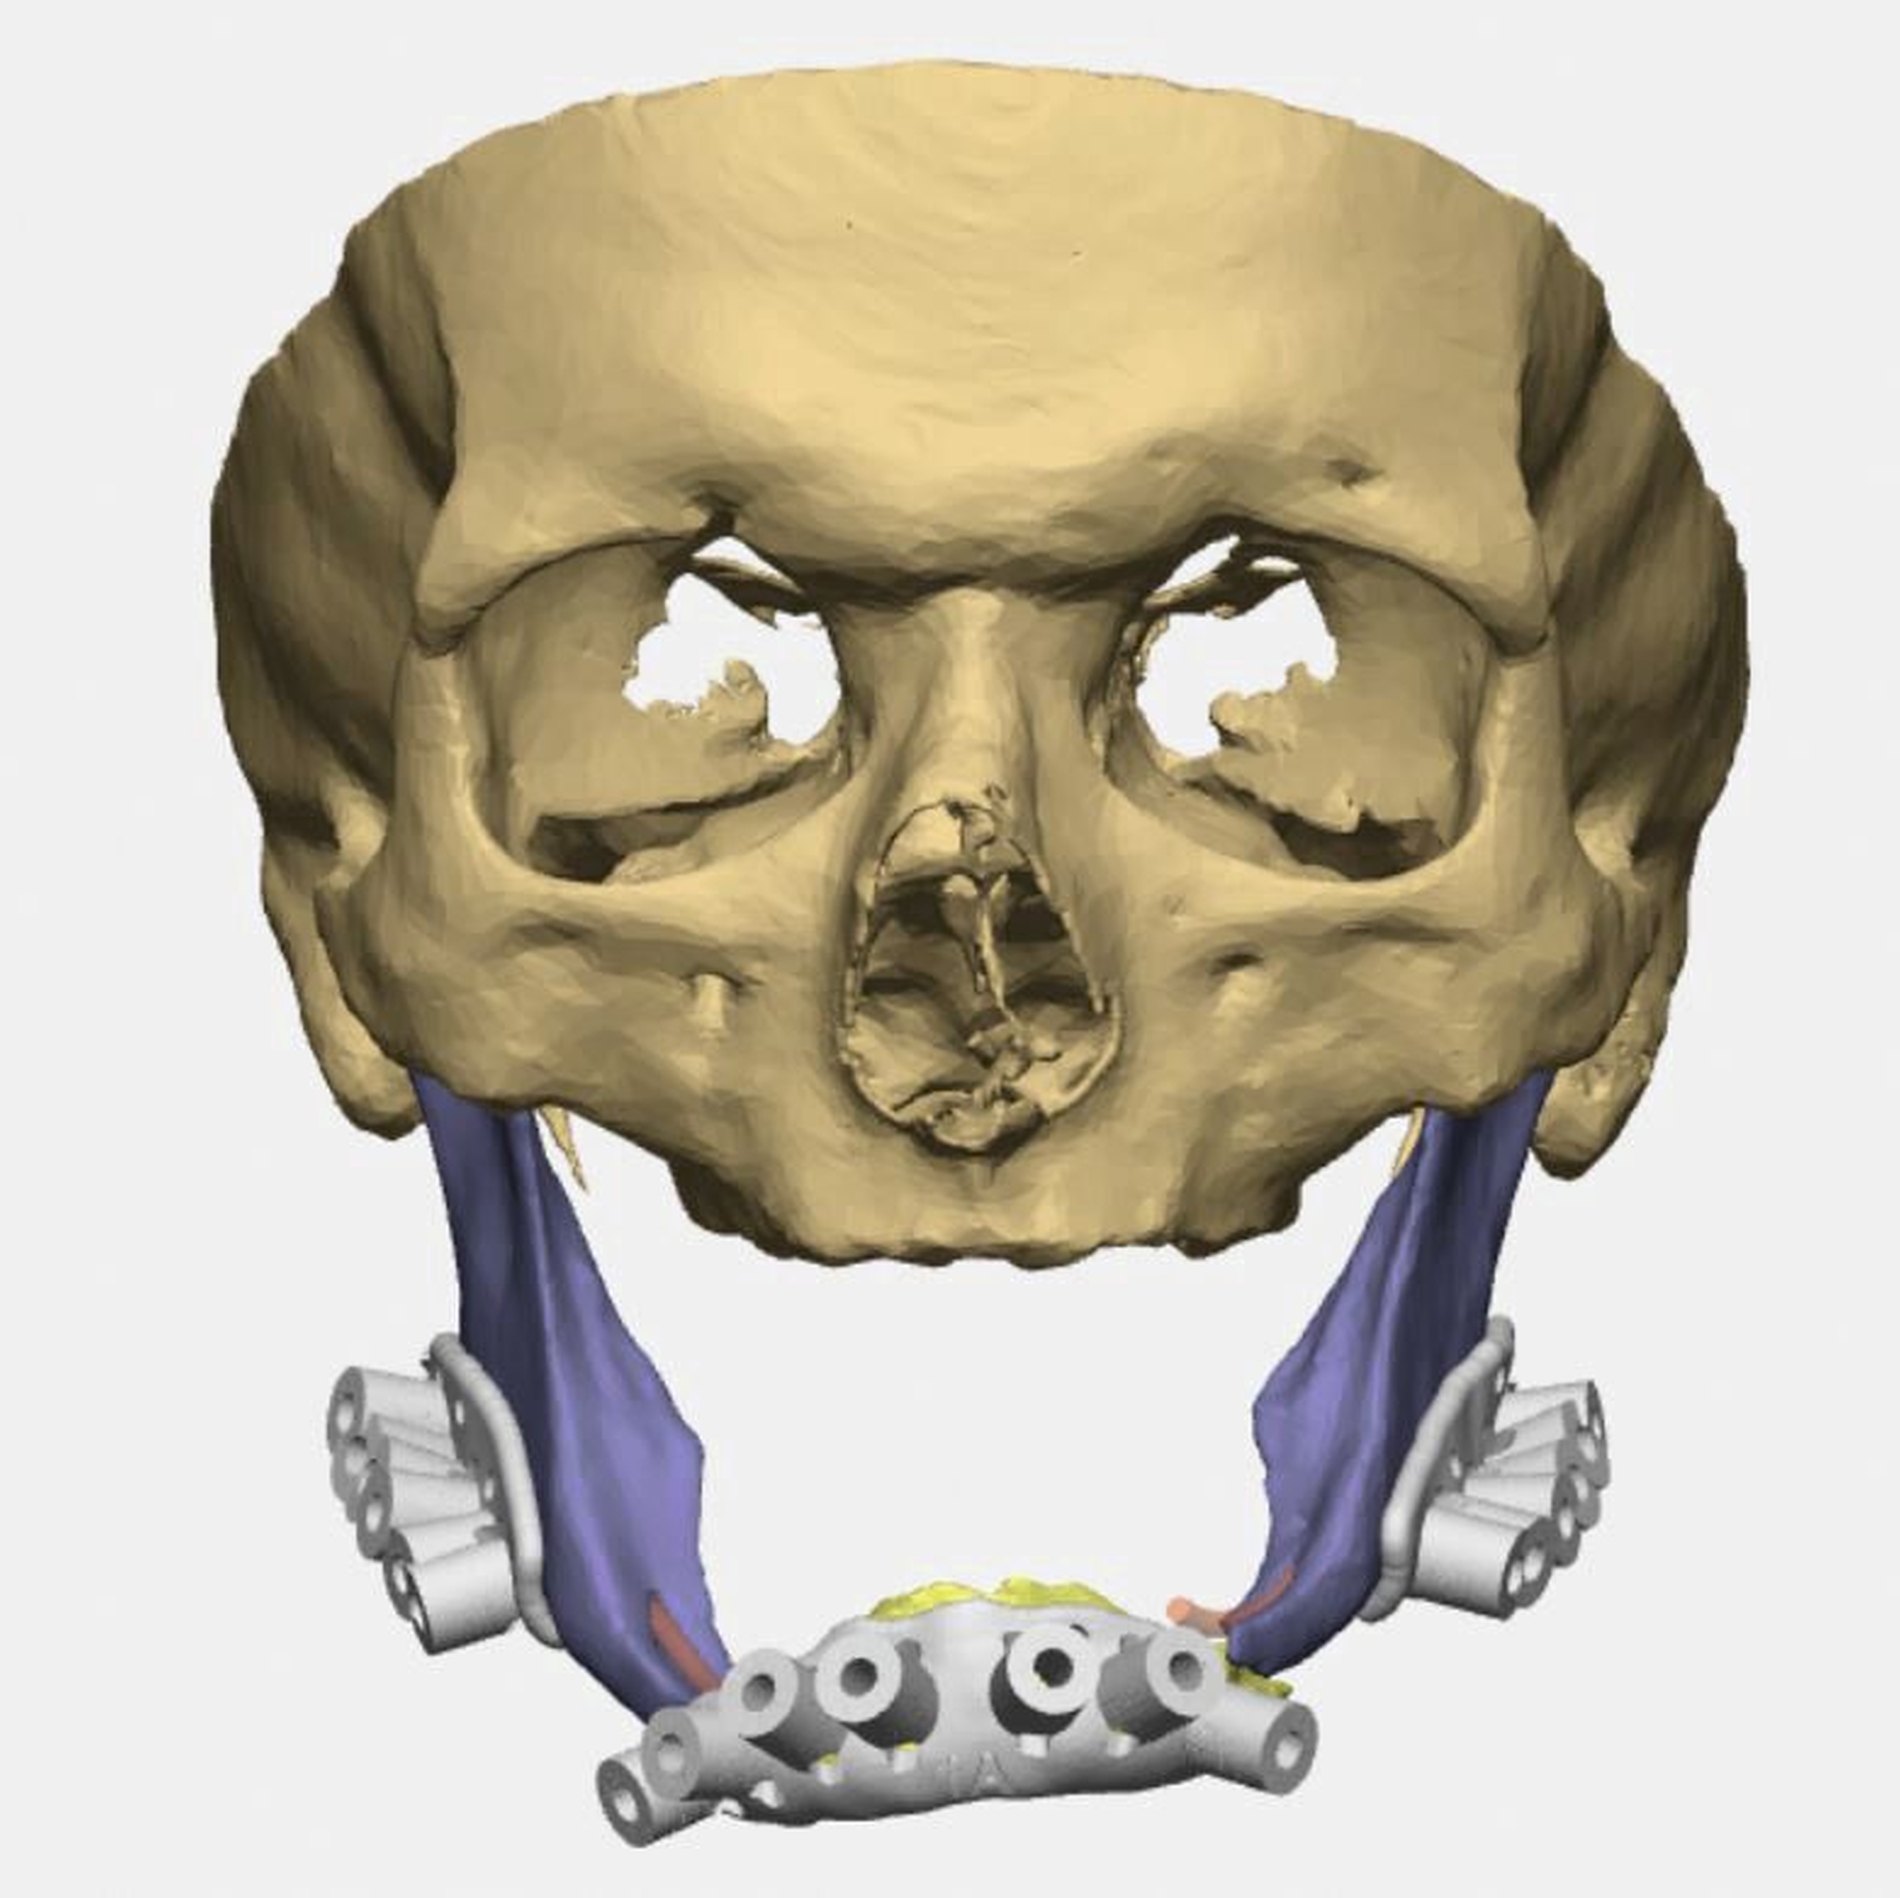

Bei zahnlosem Ober- und Unterkiefer erfolgte die virtuelle Repositionierung des frakturierten Unterkiefers (Abbildung 2a). Mittels CAD/CAM-Verfahren wurde eine stabile Rekonstruktionsplatte aus Titan (patientenspezifisches Implantat; PSI) geplant und hergestellt. Dabei sollte die Position des PSIs im Bereich des Unterkieferkorpus weit kaudal an der Basis sein, so dass später bei der Anpassung einer neuen Unterkieferprothese keine Interferenzen auftreten (Abbildung 2b).

Gleichzeitig konnte durch eine optimierte Bohrlochposition der Nervus alveolaris inferior geschont werden, eine Neurolyse brauchte nicht geplant zu werden. Außerdem wurden an die Zielreposition angepasste Bohrschablonen (drilling guides) hergestellt, die ein Vorbohren der späteren Schraubenlöcher in der exakten Zielposition ermöglichen (Abbildung 2c). In Kombination mit dem PSI sollte so eine Auto-Reposition des Unterkiefers durch die vorgegebenen Bohrlöcher erfolgen.